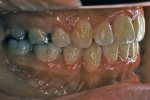

カテゴリー:ClassⅡ division 2 malocclusion (Overbite 5mm以上; 抜歯症例)

しかし、出題基準にも書いてあるように、このケースは欧米の白人によく見られるケースで、東洋人にはきわめて稀である。そこで類似ケースとして過蓋咬合(かがいこうごう)のケースを代替えとして認めるという配慮をしている。過蓋咬合とは非常に強く深く咬んでいる状態を言う。Overbiteとは前歯の垂直的な重なり具合を示す数値で、5mm以上だと上の前歯が下の前歯をほとんど覆い尽くしている感じになるので、前から見ると下の前歯はほとんど見えない状態になる。こういう状態が典型的な過蓋咬合である。典型的なclassⅡ,division 2のケースは過蓋咬合を合併している。

| 初診時